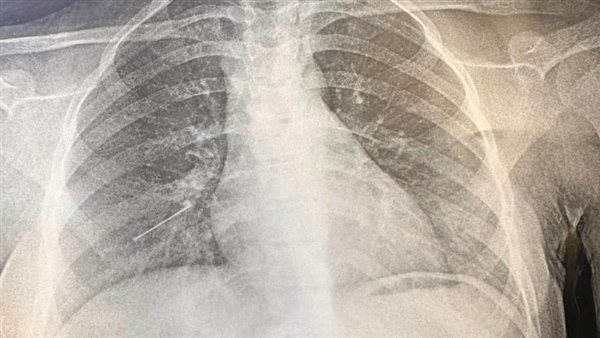

وأوضح الدكتور عمرو الدخاخني المدير التنفيذي لمستشفيات بنها الجامعية، أن الجراحة الثانية كانت عملية جراحة صدر لطفلة تبلغ من العمر 7 سنوات، تعاني من التصاقات صديدية بالرئة اليمنى، وتم إجراء عملية تقشير كامل للرئة اليمنى، عن طريق شق صدرى محدود وتم نقل المريضة للقسم الداخلى لاستكمال العلاج.

أما الحالة الثالثة فكانت جراحة صدر عاجلة لمريضة تبلغ من العمر 15 عاما تعانى من وجود جسم غريب "دبوس"، بالشعب الهوائية اليمنى البعيدة عن متناول المنظار الشعبي، وتم على الفور إجراء عملية جراحية واستخراج الجسم الغريب عن طريق شق صدري صغير محدود جدا وتم نقل المريضة للقسم الداخلى لاستكمال العلاج.